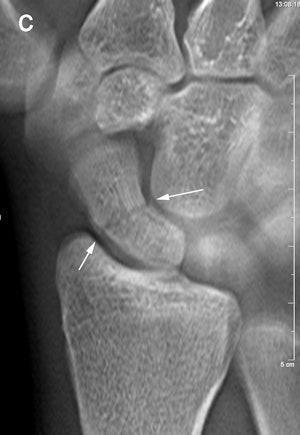

Ninety percent of scaphoid fractures heal successfully after early diagnosis and treatment, but missed fractures may lead to nonunion or avascular necrosis of the proximal fragment. Either complication can result in scaphoid nonunion advanced collapse.

Up to now, digital x-ray tomosynthesis has not been considered for this application. The technology has the ability to demonstrate cortical fractures and fractures of the trabecular bone with some degree of displacement, Geijer wrote. In that respect, its performance is similar to CT.

The trends identified in the pilot study were strong enough to conclude that tomosynthesis can detect occult fractures not visible on radiography.

"The study is noteworthy in that it has shown that radiographically occult fractures can be detected by tomosynthesis, and thus potentially reduce the number of complications after a scaphoid fracture," he wrote to AuntMinnie.com.

The experience also taught the participating radiologists that detecting fractures with tomosynthesis is somewhat different than with conventional radiography and CT. Fracture detection is mainly based on edge disruption with tomosynthesis because the structure of the medullary bone is blurred and not as distinct as in CT, Geijer noted.

Fracture detection was aided on the lateral borders by the ability to visualize the scaphoid bone cortex. Fractures could also be appreciated on the most dorsal and palmar sections because of good contrast between the bone and surrounding soft tissue or medullary bone, he wrote.